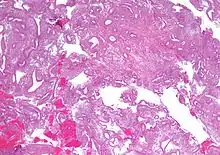

- Atypical endometrial hyperplasia (simple or complex) - Simple or complex architectural changes, with worrisome (atypical) changes in gland cells, including cell stratification, tufting, loss of nuclear polarity, enlarged nuclei, and an increase in mitotic activity. These changes are similar to those seen in true cancer cells, but atypical hyperplasia does not show invasion into the connective tissues, the defining characteristic of cancer. The previously mentioned study found that 22% of patients with atypical hyperplasia eventually developed cancer.[6]

In patients with samples showing atypia, carcinoma is already present in over 40% of cases.[11][12] Given this, the aforementioned 28% atypia progression rate may be an underestimate, and the true number may closer to the 42.5% part of the study's remarkably wide confidence interval.